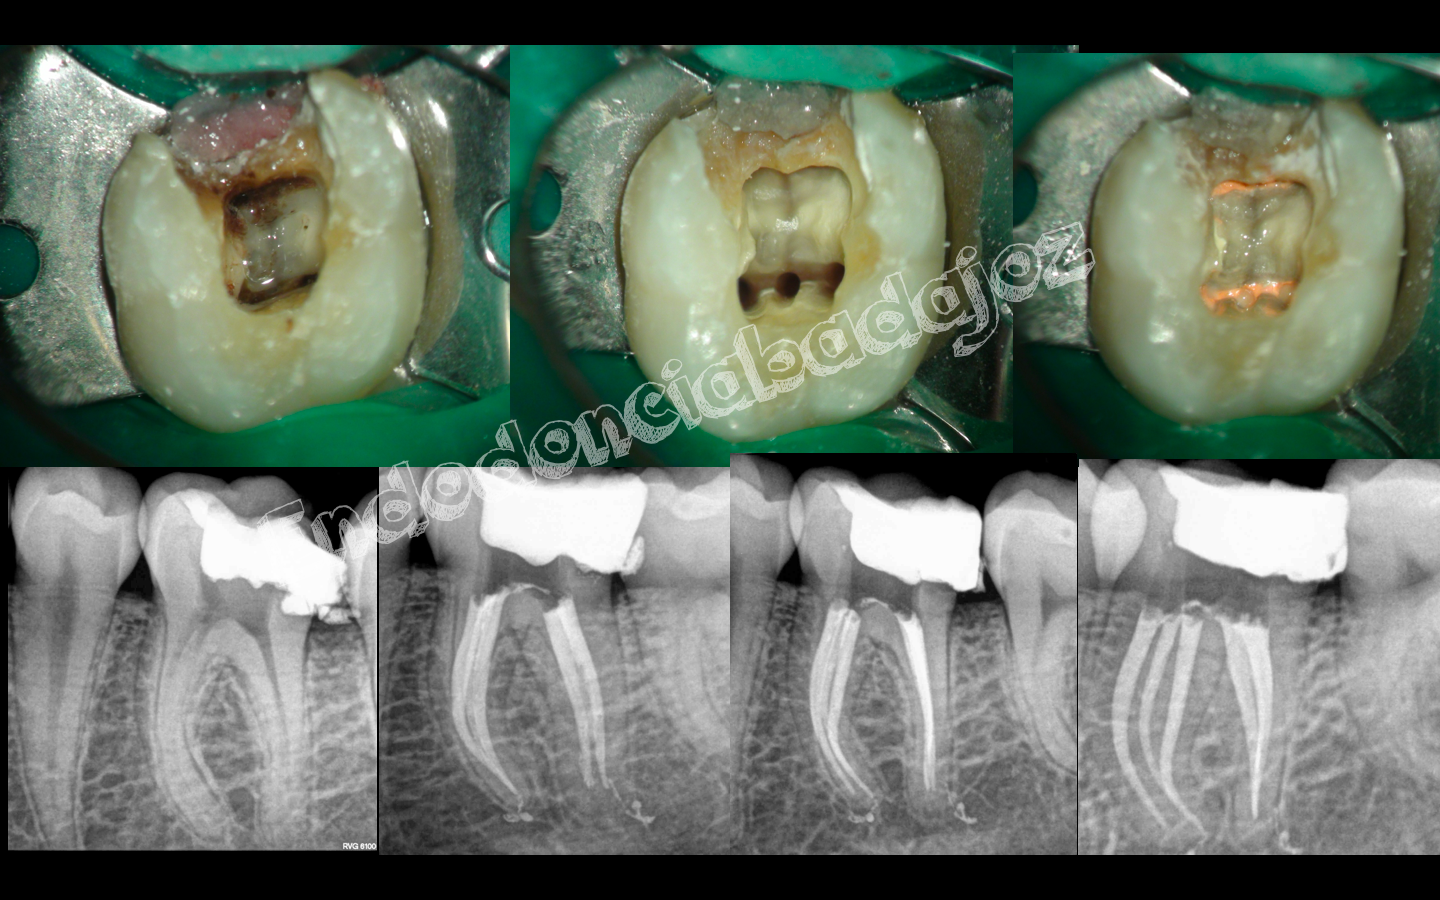

Después de una temporada sin postear ningún caso, hoy me levanté con ganas de publicar alguno, se trata de cinco casos, a mi juicio, interesantes, cuatro endodoncias de molares inferiores con anatomías complicadas y un retratamiento de un molar superior . Espero que os gusten.